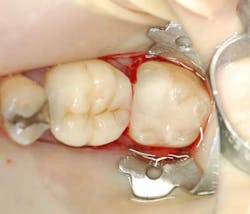

A 55-year-old male patient presented with a chief complaint of occasional hot and cold sensitivity involving his lower molar. Upon clinical examination, it was determined he had a failing amalgam and undermined mesial buccal cusp involving his second molar (Fig. 1). As per the Morgan and Presley’s prewedge protocol, a medium wedge was placed between the molars to initiate separation and protect the papilla. Upon removal of the old restoration and decay, it was decided to restore this tooth with a posterior composite material using the ABC Wedge. With a little imagination, this wedge looks like an elephant’s head and its parts will be described as such. The ears were designed to support the sectional band in three dimensions (3-D) and prevent the sectional rings from crushing in the matrix band (Fig. 2). The elephant’s trunk is analogous to the anatomic wedge. Two wedges were used from the buccal and lingual surfaces, and the curved trunks slide past each other to seal off the gingival floor (Fig. 3). A central groove is located on the back between the ears to line up the sectional separating ring and directs the pressure interproximally for maximum separation. The tooth was then easily restored in incremental layers, trimmed back, and the bite was adjusted (Fig. 4).